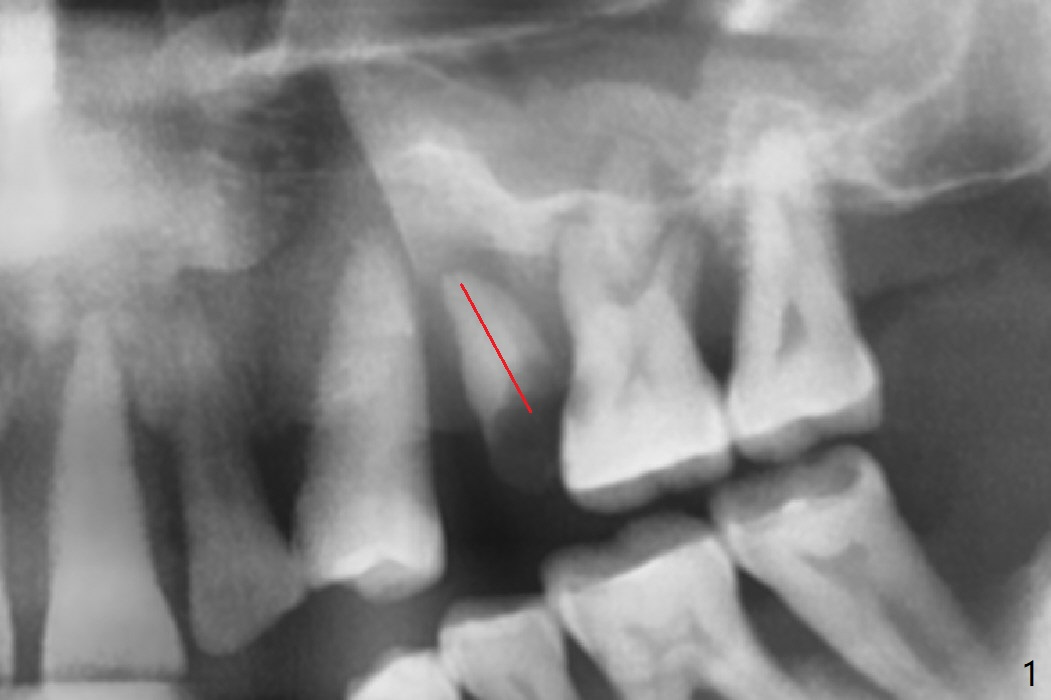

There is more bone apical to the residual root at #13 (Fig.1 red line). An immediate implant along the long axis of the root can be longer, 11.5 mm, favorable for primary stability (Fig.2 (CT taken immediately preop)). The initial trajectory is not ideal (Fig.3). When the pointed/Lindamann bur is removed (Fig.4), effort is made to move the apical end of the osteotomy distal (Fig.5 red arrow) by removing the apical bone (red dashed line). Following sequential osteotomy, a 4x10 mm dummy implant is placed with the trajectory remaining not so ideal (Fig.6,7). As the dummy implant is removed (Fig.8), a new osteotomy is established distal to the existing one (Fig.9). Subsequent drills gradually shift into the original osteotomy (Fig.10 red arrow). When the same dimension dummy implant returns, the trajectory improves with decreased stability (Fig.11). It seems reasonable to place a larger implant without further osteotomy. After placing PRF membrane and Vanilla graft for sinus lift (Fig.13 *), a 4.5x10 mm definitive implant is placed with loss of control in the trajectory (Fig.12,13).

When the initial osteotomy is off substantially (Fig.4), an osteotomy should be established de novo and as early as possible (Fig.14) so that subsequent osteotomy will not relapse to a great extent. More ideally, the initial osteotomy should be planned correctly (Fig.15,16) with sacrifice of the bone height. Nearly 1 month postop, the 4.5x5.5(5) cementation abutment is loose. When it is removed, the patient feels pain from the implant. A 5.5x6 mm healing abutment is placed instead. The implant osteointegrates with trabecular pattern in the sinus 9 months postop (Fig.20 *). The gingiva around the crown at #13 is healthy 1 year 4 months post cementation (Fig.18). Check the distal surface of #13 for bone loss if the tooth #14 is to be extracted.